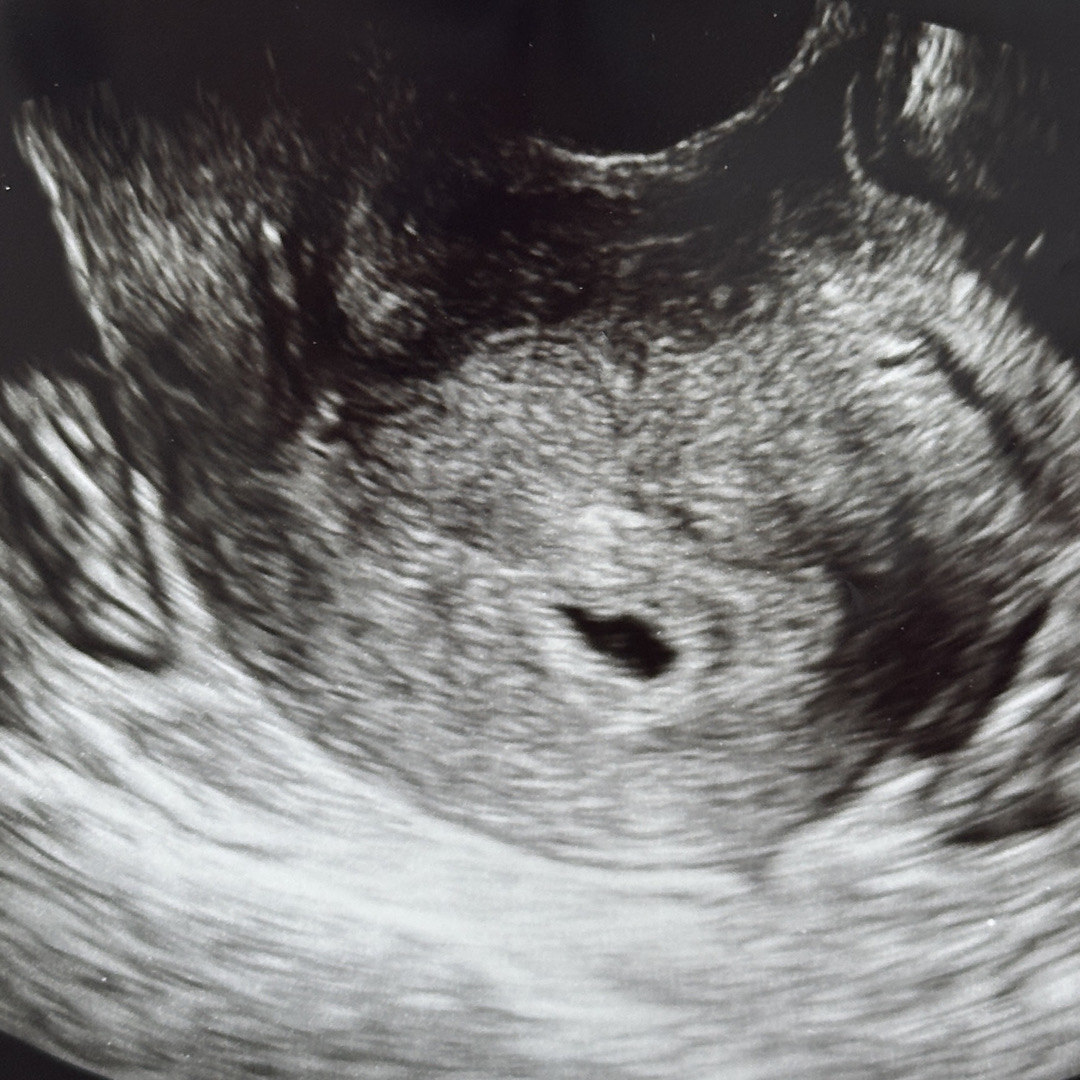

임신테스트기 역전을 확인하고 오늘 처음 초음파를 하러 갔습니다..! 마지막 생리시작일 기준 5주1일째 되는 날이였는데 초음파하면서 아기집이 보이지만 계산한 주수보다 아기집이 작다고 얘기하셨어요(0.55cm) 현재 4주3일정도라고 하시며 난황으로 추정되는게 살짝 보이는거같다 말해주셨는데 제 눈에는 안보여서 그때부터 긴장되고 너무 불안하더라구요,, 받아온 초음파사진에 동그란게 살짝 보이는거같기도한데,, 난황이라고 믿고싶은건지... 불안해서 아침에 진료보고 와서 하루종일 인터넷만 찾아보고있어요ㅠㅠ 사진 함께 봐주시면 감사하겠습니다..

사진에선 안 보이고 그 시기에 원래 난황 안 보여요 불안해하실 필요 전혀 없고 마음 편하게 2주만 더 기다려보세요